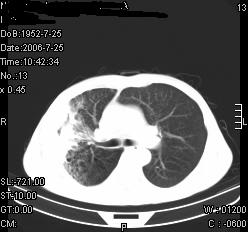

患者,男,54岁,咳嗦,咳痰20天。抗炎治疗2周。现esr76mm/h,目前患者症状明显好转,但发现两次ct片未见明显变化。两次分别做与7.25、7.31。第一次诊断右肺上叶炎症累计胸膜。大家看,从影像上内排除结核吗?

结核的可能性非常大,右上肺病变应该考虑干酪性肺炎。理由:

1.纵隔内多发淋巴结肿大。

2.esr76mm/h。

3.虽经抗炎治疗肺窗病灶有所吸收、减小,但纵隔窗病灶形态、密度、范围无明显变化。如果是单纯的大叶性肺炎,“抗炎治疗2周,目前患者症状明显好转”病灶应该基本消散了,至少也处于吸收消散期,密度变淡、范围变小。同时本病例所示其内的密度不均匀,见多发大小不一空洞样影也不符合大叶性肺炎吸收消散期表现。

病灶特点:片状 索条 结节混杂影,部分融合,密度不均,广泛累及相应胸膜.

临床治疗;二周未吸收.但症状好转.

多考虑:肺结核.